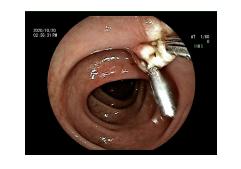

肠镜检查发现距离肛门50cm处结肠息肉

经肠镜特殊处理